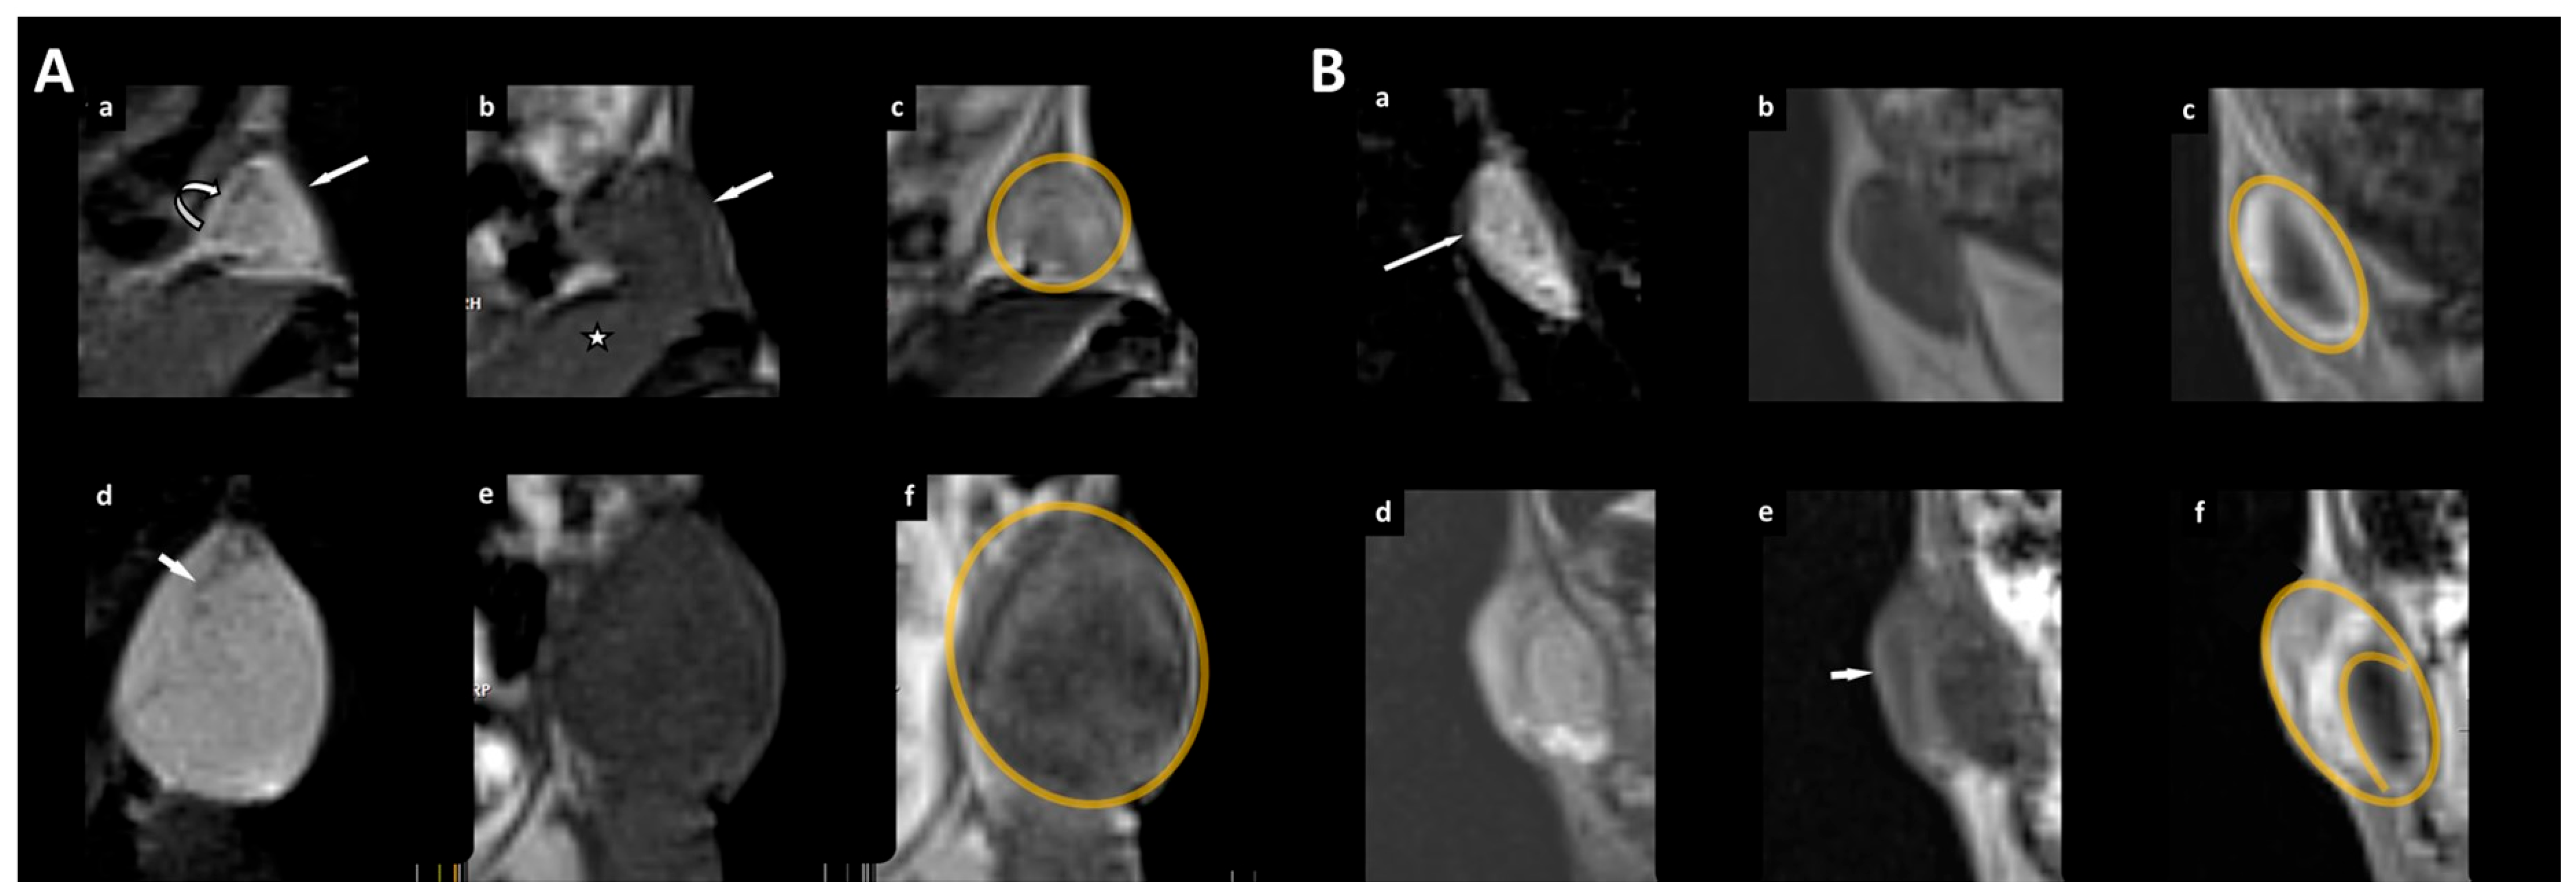

Evaluating the qualitative MR parameters, we found that areas of necrosis were only in the control group (3/7), whereas neovascular proliferation was observed in both groups (1/6 in the treatment group vs. 4/7 in the control group) (Table 4). Fisher’s exact test revealed that the pattern of tumor growth (eccentric versus concentric) was significantly different between the two groups (p < 0.05) (Figure 5; Table 4).

Furthermore, we found that the tumor volumes increased in both of our groups over time but were stronger in the control group, albeit not statistically significant. However, the pattern of tumor growth was significantly different: While tumor growth remained concentric in the control group (Figure 4), an eccentric growth behavior with a local focus was observed in the treatment group (Figure 5). Interestingly, Aliewa et al. found in their experimental study on mice glioma that two different types of border configurations contributed to tumor cell spreading through distinct invasion patterns: an invasive margin that executes slow but directed invasion and a diffuse infiltration margin with fast but less directed movement [32]. Based on these considerations, we assume that if cells continue to grow unhindered, there is concentric growth, with all cells around the edge showing a comparable potential for dividing or proliferating. In the treatment group, there was a temporary, partial arrest of the tumors showing only eccentric growth. We attribute this observation to a possible intratumoral effect of orlistat due to partial tumor suppression, which may have occurred at an early stage during treatment. In addition, structural changes in tumor appearance may well be supported by a replacement of de novo fatty acid synthesis with that of sterol precursors.

Figure 5. Example of unhindered tumor growth of the xenograft in the right flank of an immunodeficient female mouse (A) and example of a xenograft treated with orlistat (B). (A,B) (ac) timepoint of randomization, (df) last MR examination before sacrificing the animal for histological workup. A triplet of the magnified tumor is given with a coronal reconstruction from the 3D T2w volume dataset with fat saturation (a,d) and of the T1w dataset (before contrast administration (b,e); after contrast administration (c,f) with a 0.3 mm slice thickness. (A) The straight arrow (a) indicates the xenograft. The margin (curved arrow) of the xenograft is visible with high signal intensity on T2w. The xenograft is isointense to the neighboring muscle (asterisk) on T1w images (b) with marked contrast enhancement (c). After unhindered tumor growth, the area on the image with the largest cross-sectional diameter of the lesion increased from 0.18 cm2 (ac) to 0.60 cm2 (df). The pattern of tumor growth is concentric (the tumor border is marked in orange in c,f). In the T2w image (d), areas with linear signal voids within the tumor (arrow) are seen as a correlate for histologically confirmed neovascular proliferation. (B) Tumor (arrow in a) before (upper row) and after treatment with orlistat (lower row). In contrast to unhindered tumor growth in (A) with a concentric growth pattern, the tumor shows eccentric growth with a focus on the lateral border and upper outer quadrant after treatment with orlistat (arrow in e; tumor border is marked in orange in c,f).